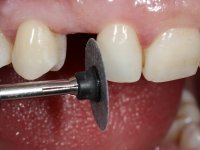

To define the dental zone to be covered by the Maryland bridge retainers, the patient was asked to perform maximum intercuspidation movements, and the contact points were marked with articular paper. Tooth preparation of the interproximal surfaces was made, to create a prosthetic insertion axis. It was sought that the mesio-distal diameter at the incisal level was equal to the diameter mesio-distal at the cervical level, that is to say, the interproximal walls were parallelized. Tooth preparation was done with fine grain diamond drills, and later polishing was done with abrasive discs. Color information was collected even before confection of the impression, to avoid dehydration of the arcade. Definitive impression was made using wash technique impression with silicone of heavy and regular consistency, both with fast setting, and a working plaster model was prepared in the lab. A laboratory scanner was used to scan the working model, and later, the infrastructure for the Maryland bridge was made using a CAD-CAM process. Ceramic was placed on this subframe. A ceramic adhesive was applied to the internal surface of the wings and connectors, which would enable bonding to the adjacent teeth. The adhesive bridge was bonded in the mouth following the conventional bonding technique. After bonding, the protrusion and laterality movements were carefully checked to avoid undesirable contacts.